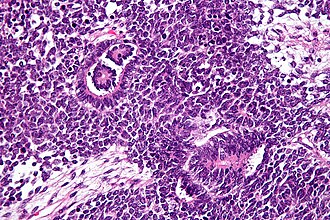

Template:Px Wilms tumour. H&E stain. | |

Features - classically three components (blastema, immature stroma, tubules):[8]

- Malignant small round blue cells ("blastema"):

- The blastemal component is the least differentiated cellular element.

- Size = ~ 2x RBC diameter.

- Nuclear pleomorphism (variation of size, shape and staining).

- Irregular nuclear membrane - important.

- Scant/difficult to discern cytoplasm - basophilic (light blue).

- Mitoses - common.

- Stroma ("immature stroma"):

- Spindle cells:

- Elliptical nuclear membrane.

- Epithelial components ("tubules"):

- Primitive rossete-like tubules, well-formed maturing and mature tubules, glomerular structures and variably papillary architecture.

- Usually clustered.

- Usu. have a central (clear/white) space surrounded by a rim of intensely eosinophilic cytoplasm.

- Nuclei of tubular structures often elongated and palisaded.